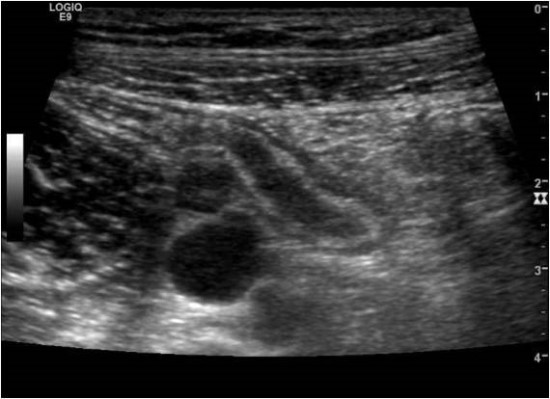

영상검사 즉, 초음파, 복부전산화단층촬영(CT)

등을 시행하면 진단율을 더 높일수가 있습니다.

복부 초음파는 가임 여성, 소아의 맹장염 진단에 유용하고,

천공, 농양 형성의 유무 등을 확인하거나

다른 질환과의 감별하는 데도 유용합니다.